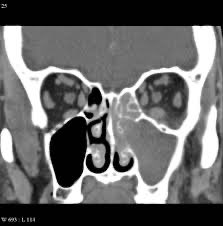

فيه نوعين اساسيين من #التهاب_الجيوب الانفية:

التهاب الجيوب الانفية الحاد (اقل من ٤ اسابيع)

التهاب الجيوب الانفية المزمن (اكثر من ٤ اسابيع)

يعرف التهاب الجيوب الانفية المزمن بوجود التالي:

١- انسداد في النفس من الانف

٢- الاحساس بالضغط او الالم او الاحتقان في الوجه

٣- وجود افرازات من الانف سواء من فتحة الانف او بصورة بلغم

٤- نقص او انعدام حاسة الشم